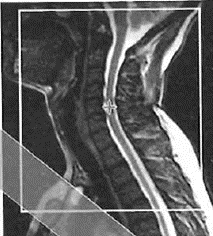

Na obrazie MR kręgosłupa lędźwiowego strzałką wskazano

Ilustracja do pytania 1

A. przepuklinę na poziomie L2-L3

B. przepuklinę na poziomie L4-L5

C. osteofit na poziomie L2-L3

D. osteofit na poziomie L4-L5